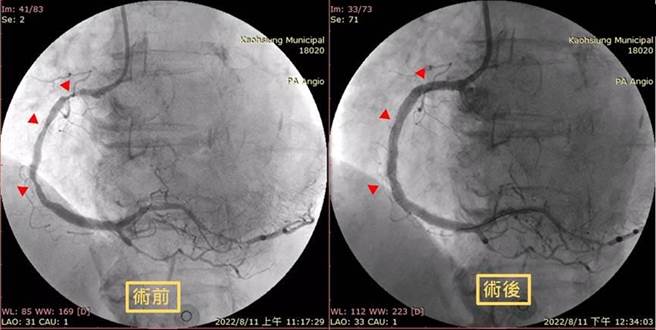

心臟团队随即启动紧急心导管手术,并放置金属涂药支架,将阻塞的右冠状动脉打通,在经过加护病房住院调养后,目前情况稳定准备要出院了。